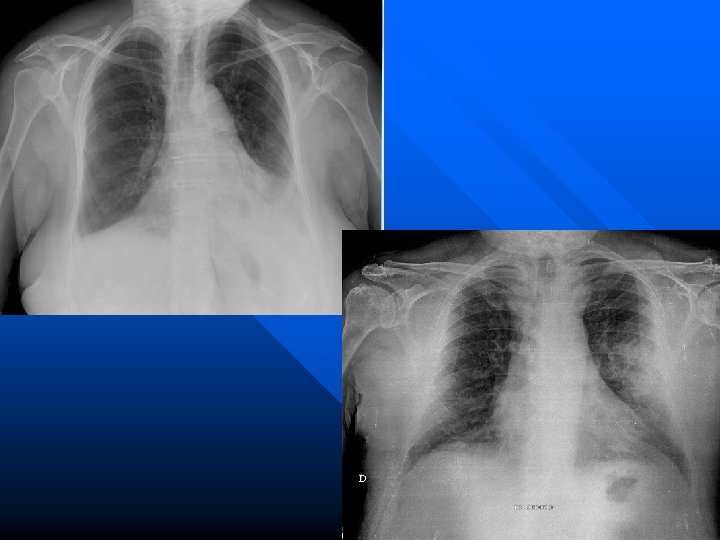

Broncopolmonite sup. dx. Rx normale dopo terapia

Broncopolmonite da Mycoplasma

Broncopolmonite da Chlamidia